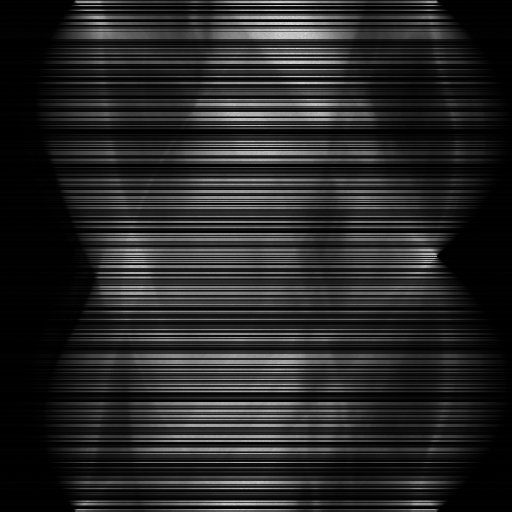

A sinogram is a 2D projection-domain representation of computed tomography (CT) data, where each row corresponds to a different acquisition angle and each column to a detector position. However, in both industrial and medical settings, acquiring full sinograms is often impractical due to radiation exposure risks or scanning time constraints. Thus, sinogram inpainting plays a vital role in CT reconstruction, enabling recovery of projection data lost due to sensor malfunction, limited-angle acquisition, or radiation dose reduction (Kalender, 2011). High-resolution sinograms, such as 2048×\times2048 or larger, are increasingly common in both synchrotron tomography and modern CT systems. In these settings, high spatial resolution is essential for capturing fine structural details and ensuring diagnostic reliability, and reducing resolution can directly compromise reconstruction quality and downstream analysis.

Sinograms are physical measurements governed by acquisition geometry. They contain highly directional structures, large smooth background regions, and frequency sparsity concentrated along specific angular bands. Their patches remain physically meaningful when isolated–they correspond to narrower angular coverage or limited detector ranges, but still represent valid projections (Slaney & Kak, 1988). In contrast, natural image patches may lose semantic context (e.g., cropping only an eye from a face image), making patch-wise inference less suitable (Zhang et al., 2023a).

As shown in Fig 1, HiSin builds upon RePaint (Lugmayr et al., 2022) as its default backbone and restructures the inference process into a three-stage resolution-guided pipeline. The sinogram is first denoised at low resolution to establish global structure, then refined at mid resolution, and finally completed at full resolution through patch-wise inference. At each stage, the upsampled output from the previous resolution is fused with the current input before denoising, ensuring hierarchical guidance across scales. This hierarchical design avoids full-frame activation and substantially reduces memory usage while preserving long-range consistency. To further improve efficiency under the structural characteristics of sinograms, HiSin introduces two inference-time modules: (1) frequency-aware patch skipping, which exploits the spectral sparsity of background regions to bypass redundant computation, and (2) structure-adaptive step allocation, which leverages local structural heterogeneity to adjust denoising depth per patch.

To efficiently inpaint high-resolution sinograms while avoiding memory overflow, HiSin adopts a three-stage progressive inference pipeline operating over low, mid, and high resolutions. Let xrx_{r} denote the input at resolution r{low,mid,high}r\in\{low,mid,high\}. Each resolution level xrx_{r} is obtained by downsampling the original sinogram using a fixed ratio: low and mid-resolution inputs correspond to 0.25×0.25\times and 0.5×0.5\times the original resolution, respectively. At the first stage, full DDIM inference is performed on xlowx_{low} to generate a coarse prior x^low\hat{x}_{low}, which captures global structural cues at minimal memory cost.